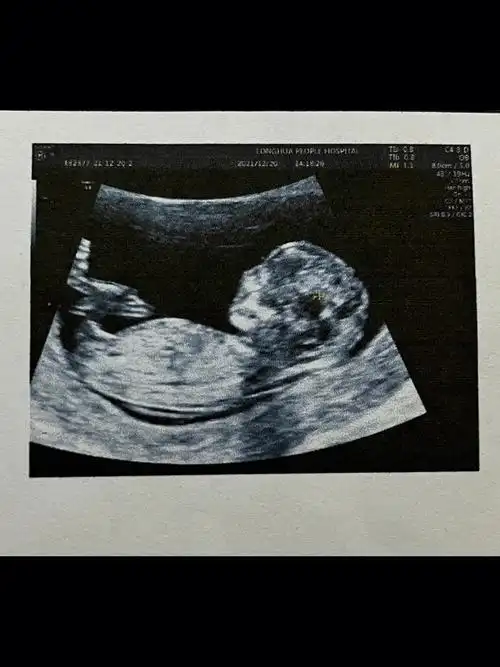

生了女孩的nt图片弯着就是男孩平是女孩吗2

是不是所有的nt图像,有三条线的都表示生女孩呢?

如果nt图是弯着的生男孩,nt图是平行的生女孩